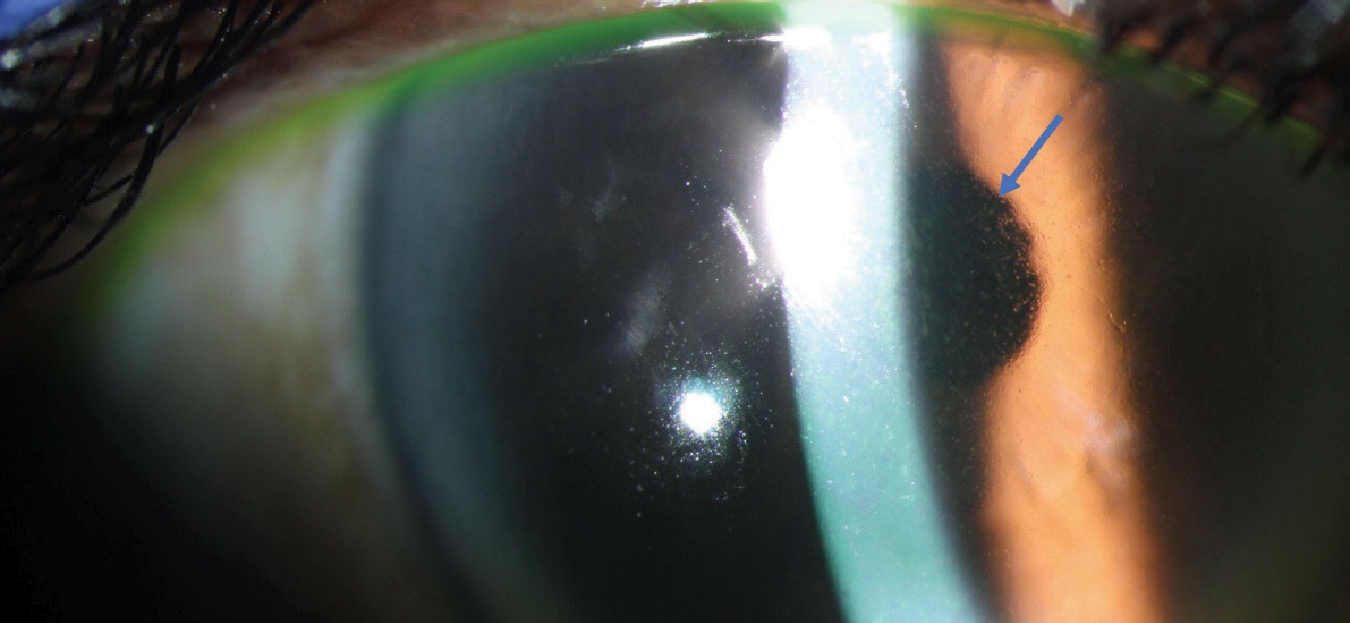

- Belantamab mafodotin (Blenrep): Causes keratopathy in patients with relapsed or refractory multiple myeloma.

- Tisotumab vedotin (Tivdak): Leads to corneal and conjunctival changes in cervical cancer patients.

- Mirvetuximab soravtansine (Elahere): Associated with keratopathy, blurred vision, and dry eyes in ovarian cancer treatments.

- Corneal damage